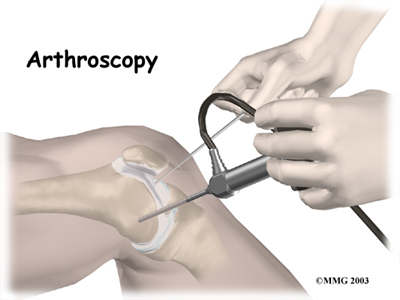

The arthroscope is a small fiber-optic tube that is used to see and operate inside the joint. It is a small metal tube about 1/4 inch in diameter (slightly smaller than a pencil) and about seven inches in length. The fiber-optics inside the metal tube of the arthroscope allow a bright light and a TV camera to be connected to the outer end of the arthroscope. The light shines through the fiber-optic tube and into the knee joint. A TV camera is attached to the lens on the outer end of the arthroscope. The TV camera projects the image from inside the knee joint onto a TV screen next to the surgeon. The surgeon actually watches the TV screen (not the knee joint) while moving the arthroscope to different places inside the knee joint.

The arthroscope is a small fiber-optic tube that is used to see and operate inside the

joint. It is a small metal tube about 1/4 inch in diameter (slightly smaller than a pencil) and about seven inches in length. The fiber-optics inside the metal tube of the arthroscope allow a bright light and a TV camera to be connected to the outer end of the arthroscope. The light shines through the fiber-optic tube and into the knee joint. A TV camera is attached to the lens on the outer end of the arthroscope. The TV camera projects the image from inside the knee joint onto a TV screen next to the surgeon. The surgeon actually watches the TV screen (not the knee joint) while moving the arthroscope to different places inside the knee joint.